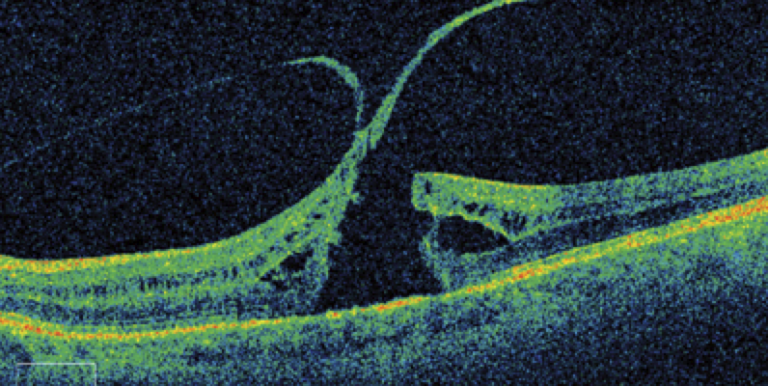

Macular Holes are a foveal full thickness defect or gap in the retina, which can also have associated cystoid macular edema. The macula is located in the center of the retina, it's primary function is to provide central and fine detail vision which is essential for simple day-to-day tasks such as reading. A macular hole in it's premature stages can cause blurry or distorted sight, straight lines may appear wavy to the patient and they may have difficulty reading small print. In an advanced stage macular hole, the patient may notice a black patch or gap in their central vision, macular holes are typically painless and do not lead to complete loss of vision. The cause of a macular hole is usually unknown, the condition typically affects patients aged between 60 and 80 years old and is more common in women compared to men. Although there is typically no identifiable cause of a macular hole, there are some risks factors that have been affiliated with it, these include previous severe injury to the eye, being very myopic (short-sighted), persistent swelling of the retina as a result of underlying conditions such as diabetes or previous eye surgery and vitreomacular traction, which is the pulling of vitreous jelly in the middle of the eye away from the macula and retina at the inferior of the eye caused by age, some of this vitreous jelly may still remain attached which can lead to a macular hole.